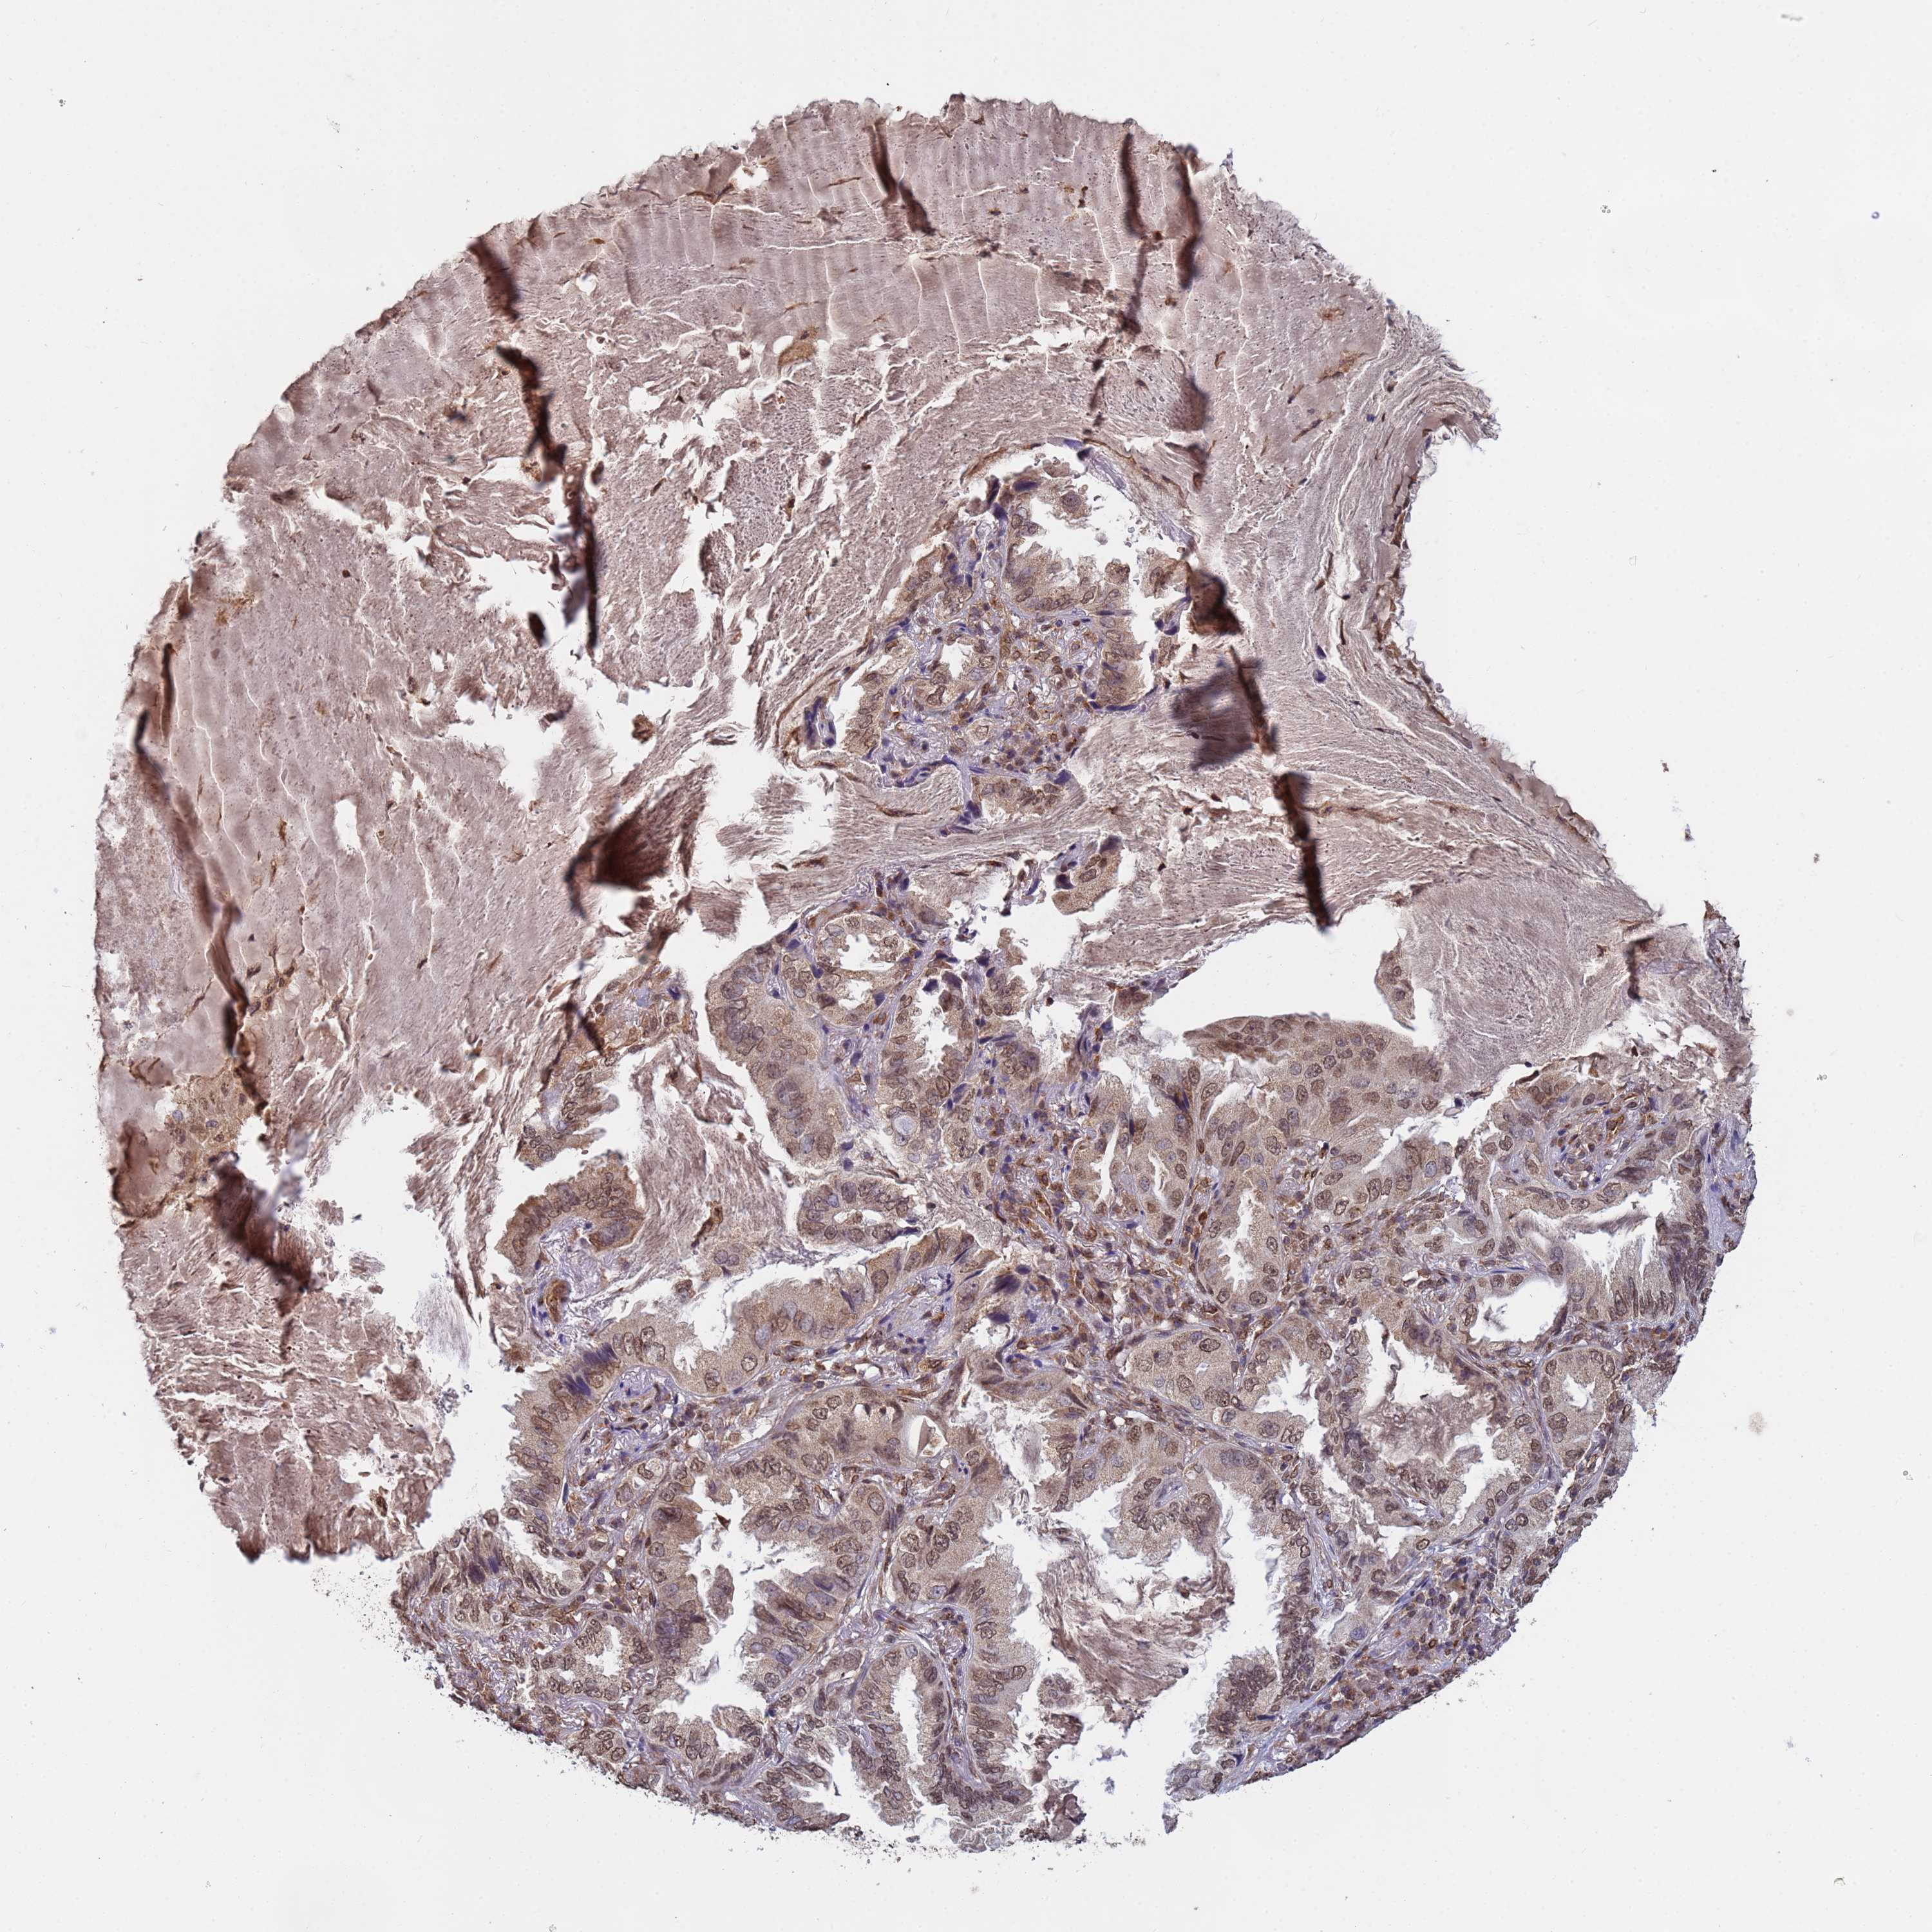

CANCER LUNG CANCER Show tissue menu

LUAD TCGA LUAD VALIDATION LUSC TCGA LUSC VALIDATION PROTEIN LUAD CPTAC PROTEIN LUSC CPTAC PROTEIN EXPRESSION